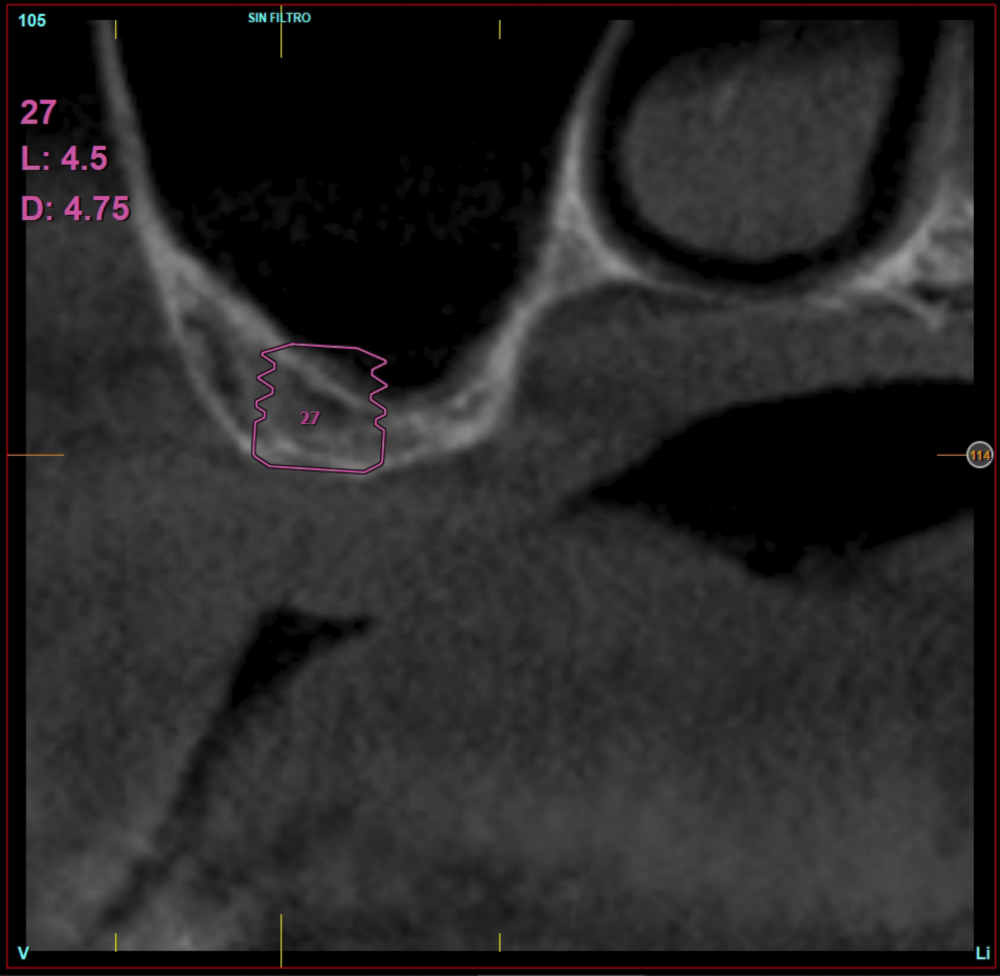

Material and method. A retrospective study has been carried out in patients in whom extra-short implants (4.5 and 5.5 mm length) were inserted directly by transcrestal elevation with residual ridges between 2 and 3 mm. The implant was the analysis unit for the descriptive statistics regarding location, implant dimensions, and radiographic measurements. The patient was the measurement unit for the analysis of age, sex and medical history. The main variable was the gain in height over the apex of the implant after 6 months of the surgery and one year after the load comparing both measurements and as secondary variables the biological complications and the implant failure were recorded.

Results. Ten patients who met the inclusion criteria were recruited and 20 implants were inserted. The mean residual bone volume height was 3.1 mm (+/- 0.3 mm with a range elevation above the apex of the implant in millimetres is of 2.8 mm (+/- 0.99 range 1.9 -5 mm). In the control cone-beam after one year of the studied load of the implants, the bone gain achieved was maintained, with no decrease in the volume gained, only three cases showed a decrease of between 0.4 and 0.5 mm of the initial volume at the end. No implants failed in the follow-up period and no biological complications were found in the surgery.

In this type of approach to the sinus, an important point is the stability of the grafted bone, located above the apex of the implant and with a bone tissue little vascularized (as usually occurs in these large atrophies with low density), so assessing what happens with the bone volume gained by this long-term procedure is also a key fact26,27. The mineralization of the bone graft and its maintenance once the implant loading is performed can make the difference in the success of the technique, especially in increasingly extreme cases. Therefore, the material used as a graft and the surface of the implant are two factors to take into account when performing this type of procedure28-31. Hydrophilic and osteoconductive surfaces in implants are of vital importance in these complex cases, as well as the filling materials that stimulate the formation of new bone28-31. The implants with UnicCa (Biotechnology Institute, Vitoria, Spain) surface, have a superhydrophilic surface. It is a very rough surface (Optima), with a calcium ions layer. This implies that the contact of blood and plasma with all points of the surface increases to the maximum the active surface for regeneration, by being completely coated with fluids due to its high capillarity. In the following series of clinical cases, patients treated by transcrestal sinus lift, with extra-short and ultra-short implants (4.5 and 5.5 mm), BTI (Biotechnology institute), of internal connection and universal plus platform in residual bone heights below 3 mm, studying the behaviour of implants regarding their survival as well as the maintenance of the bone volume achieved in the crestal elevation.